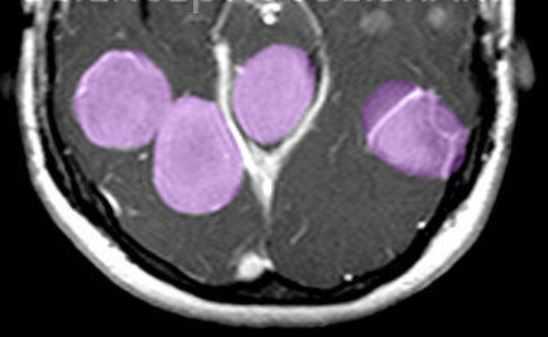

Субэпендимальные, то есть проецирующиеся в желудочек, но растущие со стороны паренхимы мозга, узлы чаще расположены рядом с хвостатым ядром или гипоталамической бороздой сразу за отверстием Монро, реже в области III, IV желудочков и Сильвиева водопровода. На Т2-взвешенных томограммах субэпендимальные узлы умеренно гиперинтенсивны и часто содержат кальцинаты . От астроцитом их отличает не столь яркий сигнал и меньшие размеры. Контрастирование при введении препаратов гадолиния иногда наблюдается и в субэпендимальных узлах , и всегда в астроцитомах.

Туберозный склероз. Субэпендимальные узлы. Аксиальная Т-зависимая МРТ.